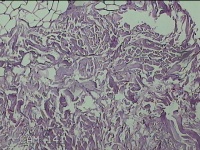

后枕部结节

性别

男

年龄

27岁

临床诊断

皮下结节

一般病史

发现后枕部结节3个月余,无明显疼痛及不适。

标本名称

大体所见

灰白暗红色结节1.3x0.8x0.3cm一个,表面糜烂,切面灰白暗红色,质软。

脂肪瘤的样子。